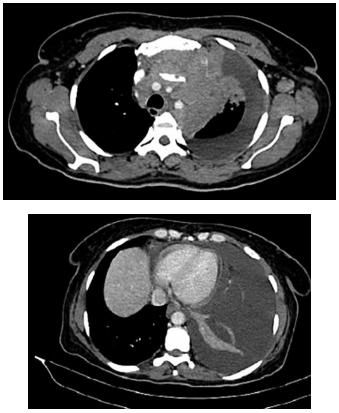

Mulher de 52 anos apresenta quadro de quatro semanas

de dispneia progressiva, dor torácica do lado esquerdo

e tosse seca. O histórico é relevante para histerectomia

para miomas uterinos há três anos. A oximetria de pulso

é de 93% em ar ambiente. Exames séricos: hemoglobina: 9,8 g/dL; d-dímero: 770 ng/mL. O ultrassom mostra

derrame pleural esquerdo, e a toracocentese revela:

líquido amarelado e levemente turvo; proteína: 6,1 g/dL;

lactato desidrogenase: 5.910 UI/L; pH: 7,44; adenosina deaminase: 12,1 UI/L; contagem de leucócitos:

157.109 células/mm3

(78% linfócitos); coloração de Gram

e cultura para bactérias e fungos permanecem negativos;

a citologia mostra linfócitos abundantes sem células malignas. Imagens da tomografia realizada são mostradas

a seguir:

(Arquivo pessoal; imagem usada com autorização)